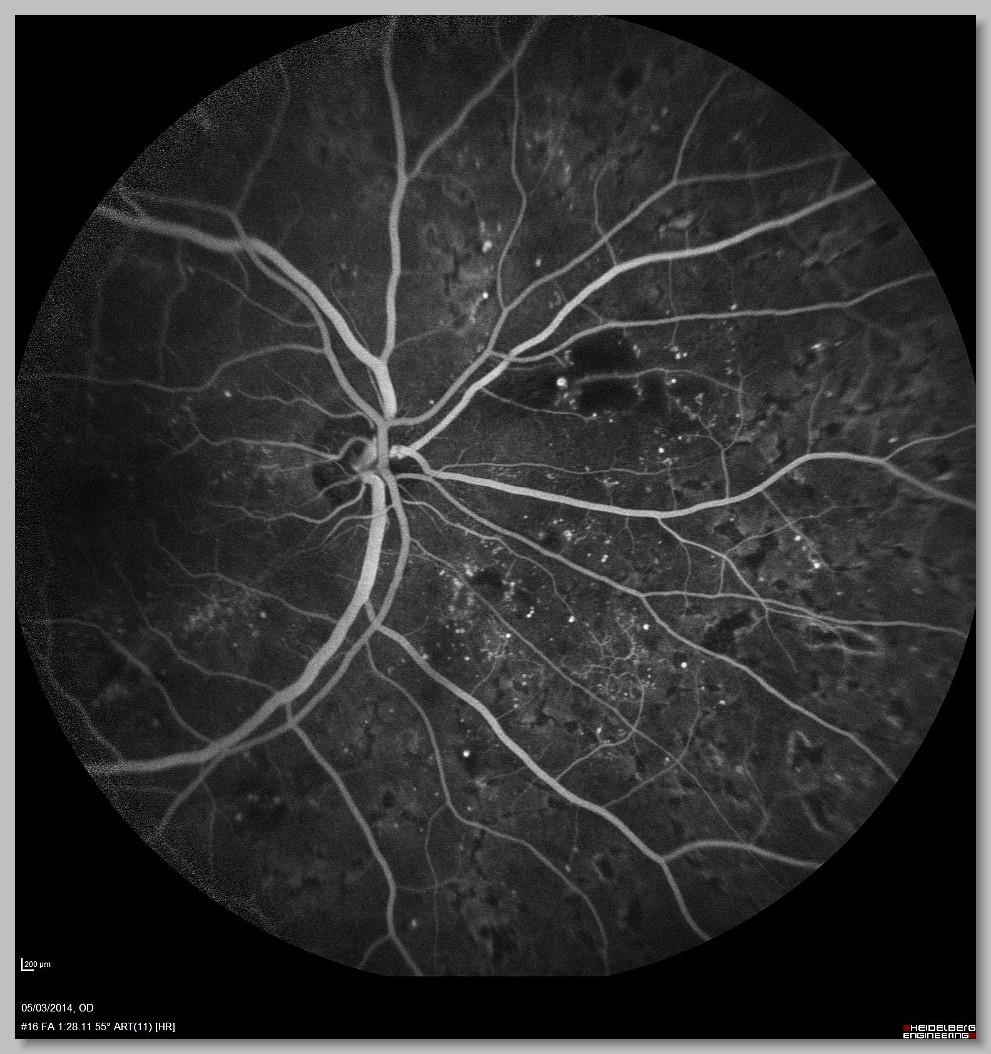

FA 002 FA 003 FA 004 FA 005